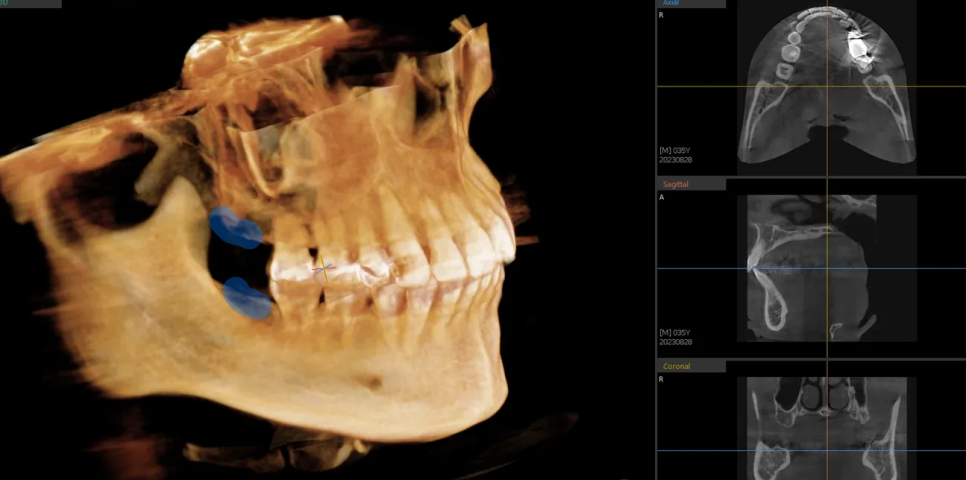

정밀사진(CT) 확인

2차원 엑스레이만으로는 정확한 뼈의 양을 판단하기 어려울 수 있습니다. 그래서 CT를 통해 3차원적으로 재확인했습니다. 결과적으로 뼈가 뒤쪽까지 충분히 존재하여, 전체 치열을 후방으로 이동시킬 수 있는 공간이 넉넉한 것을 재차 확인했습니다.

CT 사진 – 후방 뼈 공간이 충분함을 3차원적으로 확인

비발치로도 충분한 후방이동이 가능하다는 판단을 내렸습니다.